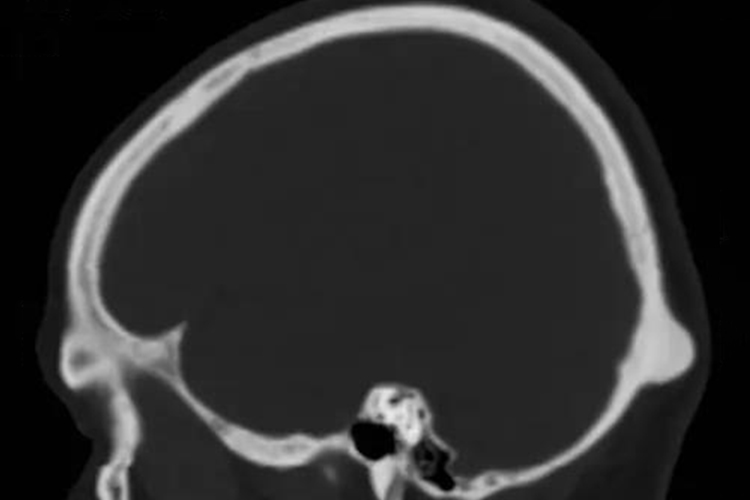

后脑勺枕骨突出可能为正常的枕外隆突,也可能是局部颅脑肿瘤、头颅畸形,导致枕骨部位形成局部隆起。

后脑勺枕骨突出可能为正常的枕外隆突,也可能是局部颅脑肿瘤、头颅畸形,不同疾病的临床症状存在差异。

常见于舟状头畸形,又称长头,主要表现为前额和枕部凸出,可导致枕骨突出的症状。